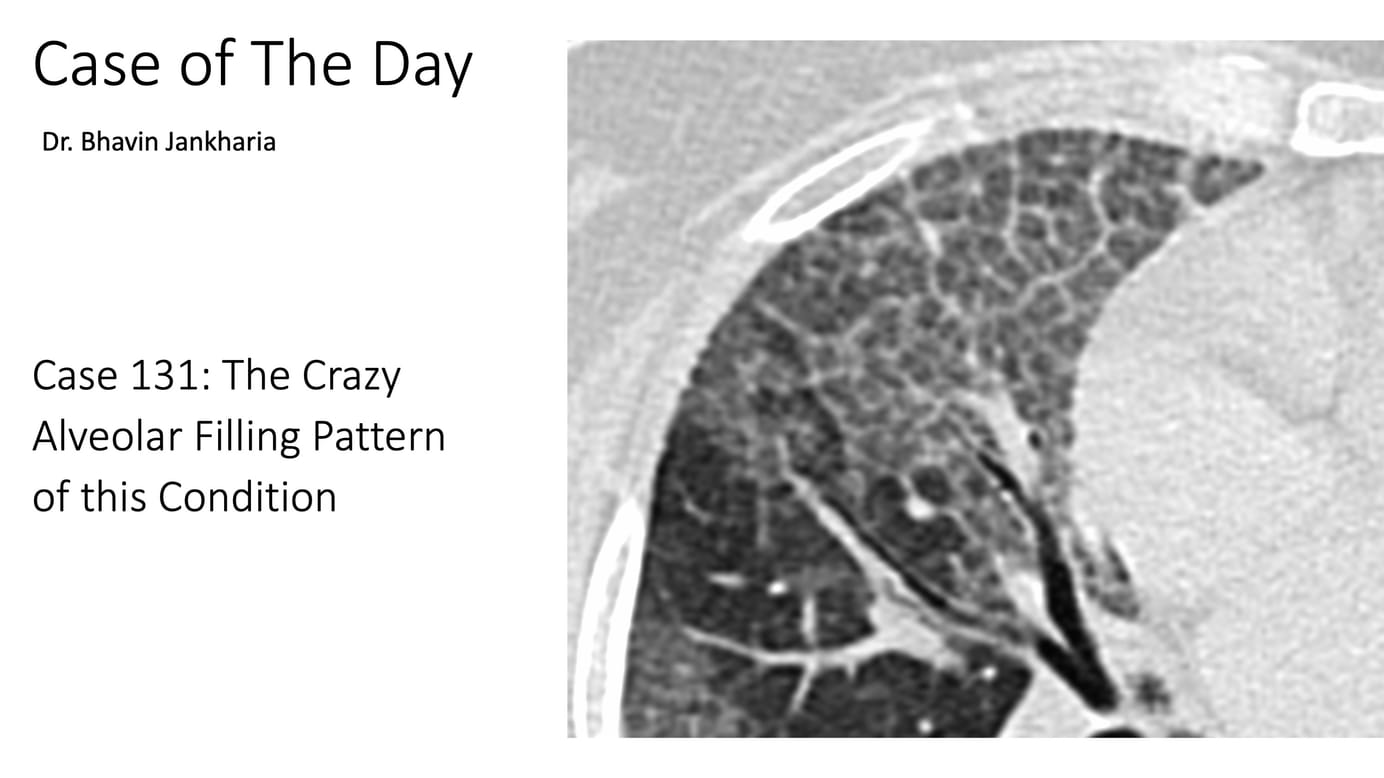

A 76-year old man presented with gradually progressive breathlessness

Thoughts?